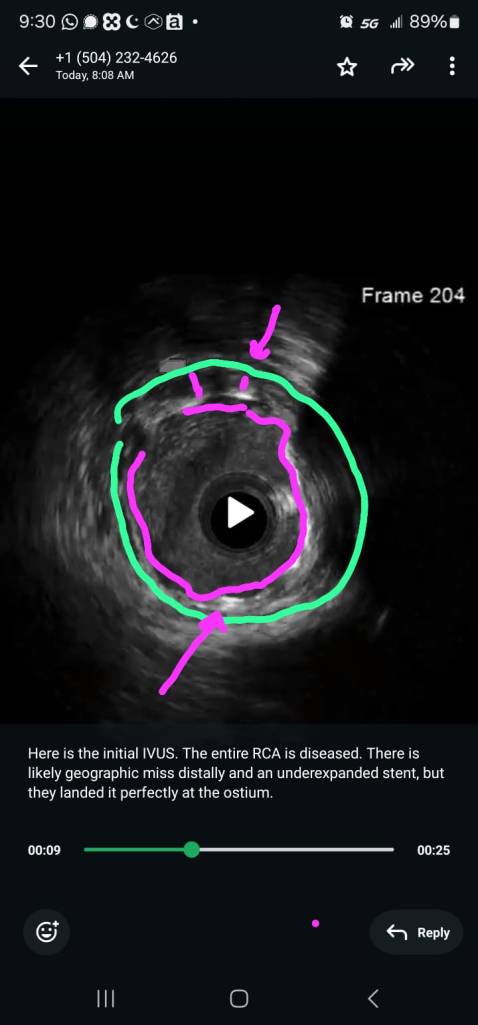

Here is the initial IVUS. The entire RCA is diseased. There is likely geographic miss distally and an underexpanded stent, but they landed it perfectly at the ostium. An AL1 is not the best guide for the remaining sequence which involves engaging and disengaging the RCA ostium. So we decided to switch guides.